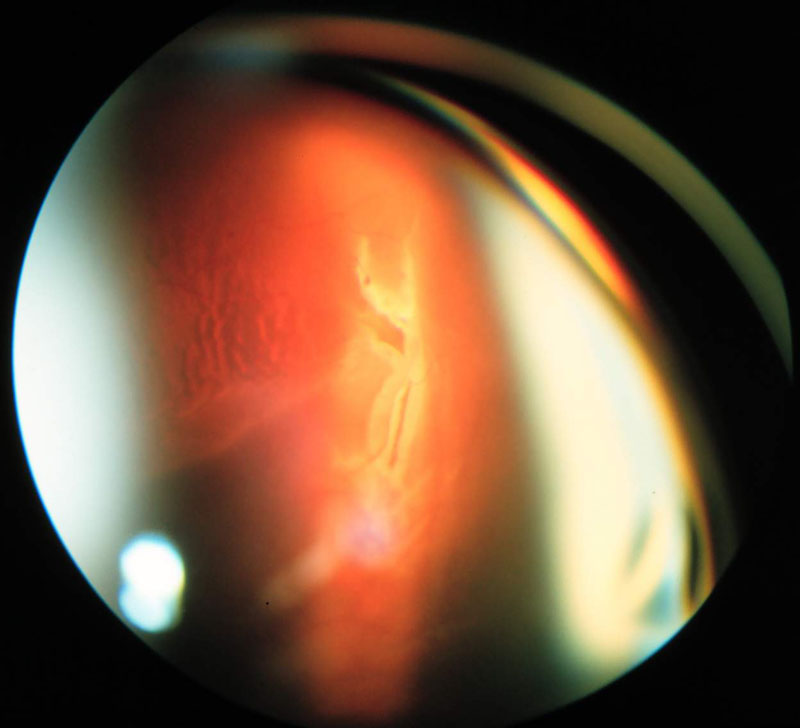

2. ábra

2. ábra Vitrectomia, siliconolaj beültetés után alul bullosus jellegű retina leválás alakult ki. A TransEquator lencsével készített felvételen a látószög az előbbinél kisebb, a kép felbontása azonban nagyobb.